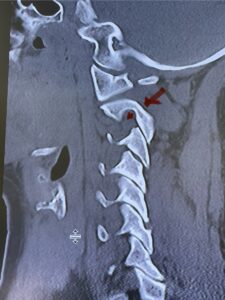

Fig. 6a: Sagittal cervical CT scan demonstrating an abnormally thin right C2 isthmus prohibiting safe placement of screw (red arrow). Notice the vertebral foramen eroding the isthmus bone structure (red dot).

Fig. 6b: Sagittal cervical CT scan demonstrating normal thickness of the left C2 isthmus (red arrow)